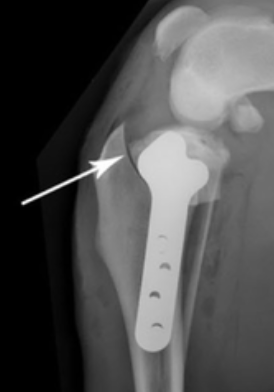

Restore Your Pet’s Comfort and Mobility

We know how hard it is to see your pet in pain. We’re here to help them heal—with skill, compassion, and heart. Our surgical team is here to help. At Pacific Paws, we provide advanced orthopedic surgical solutions designed to get your pet back on their paws.